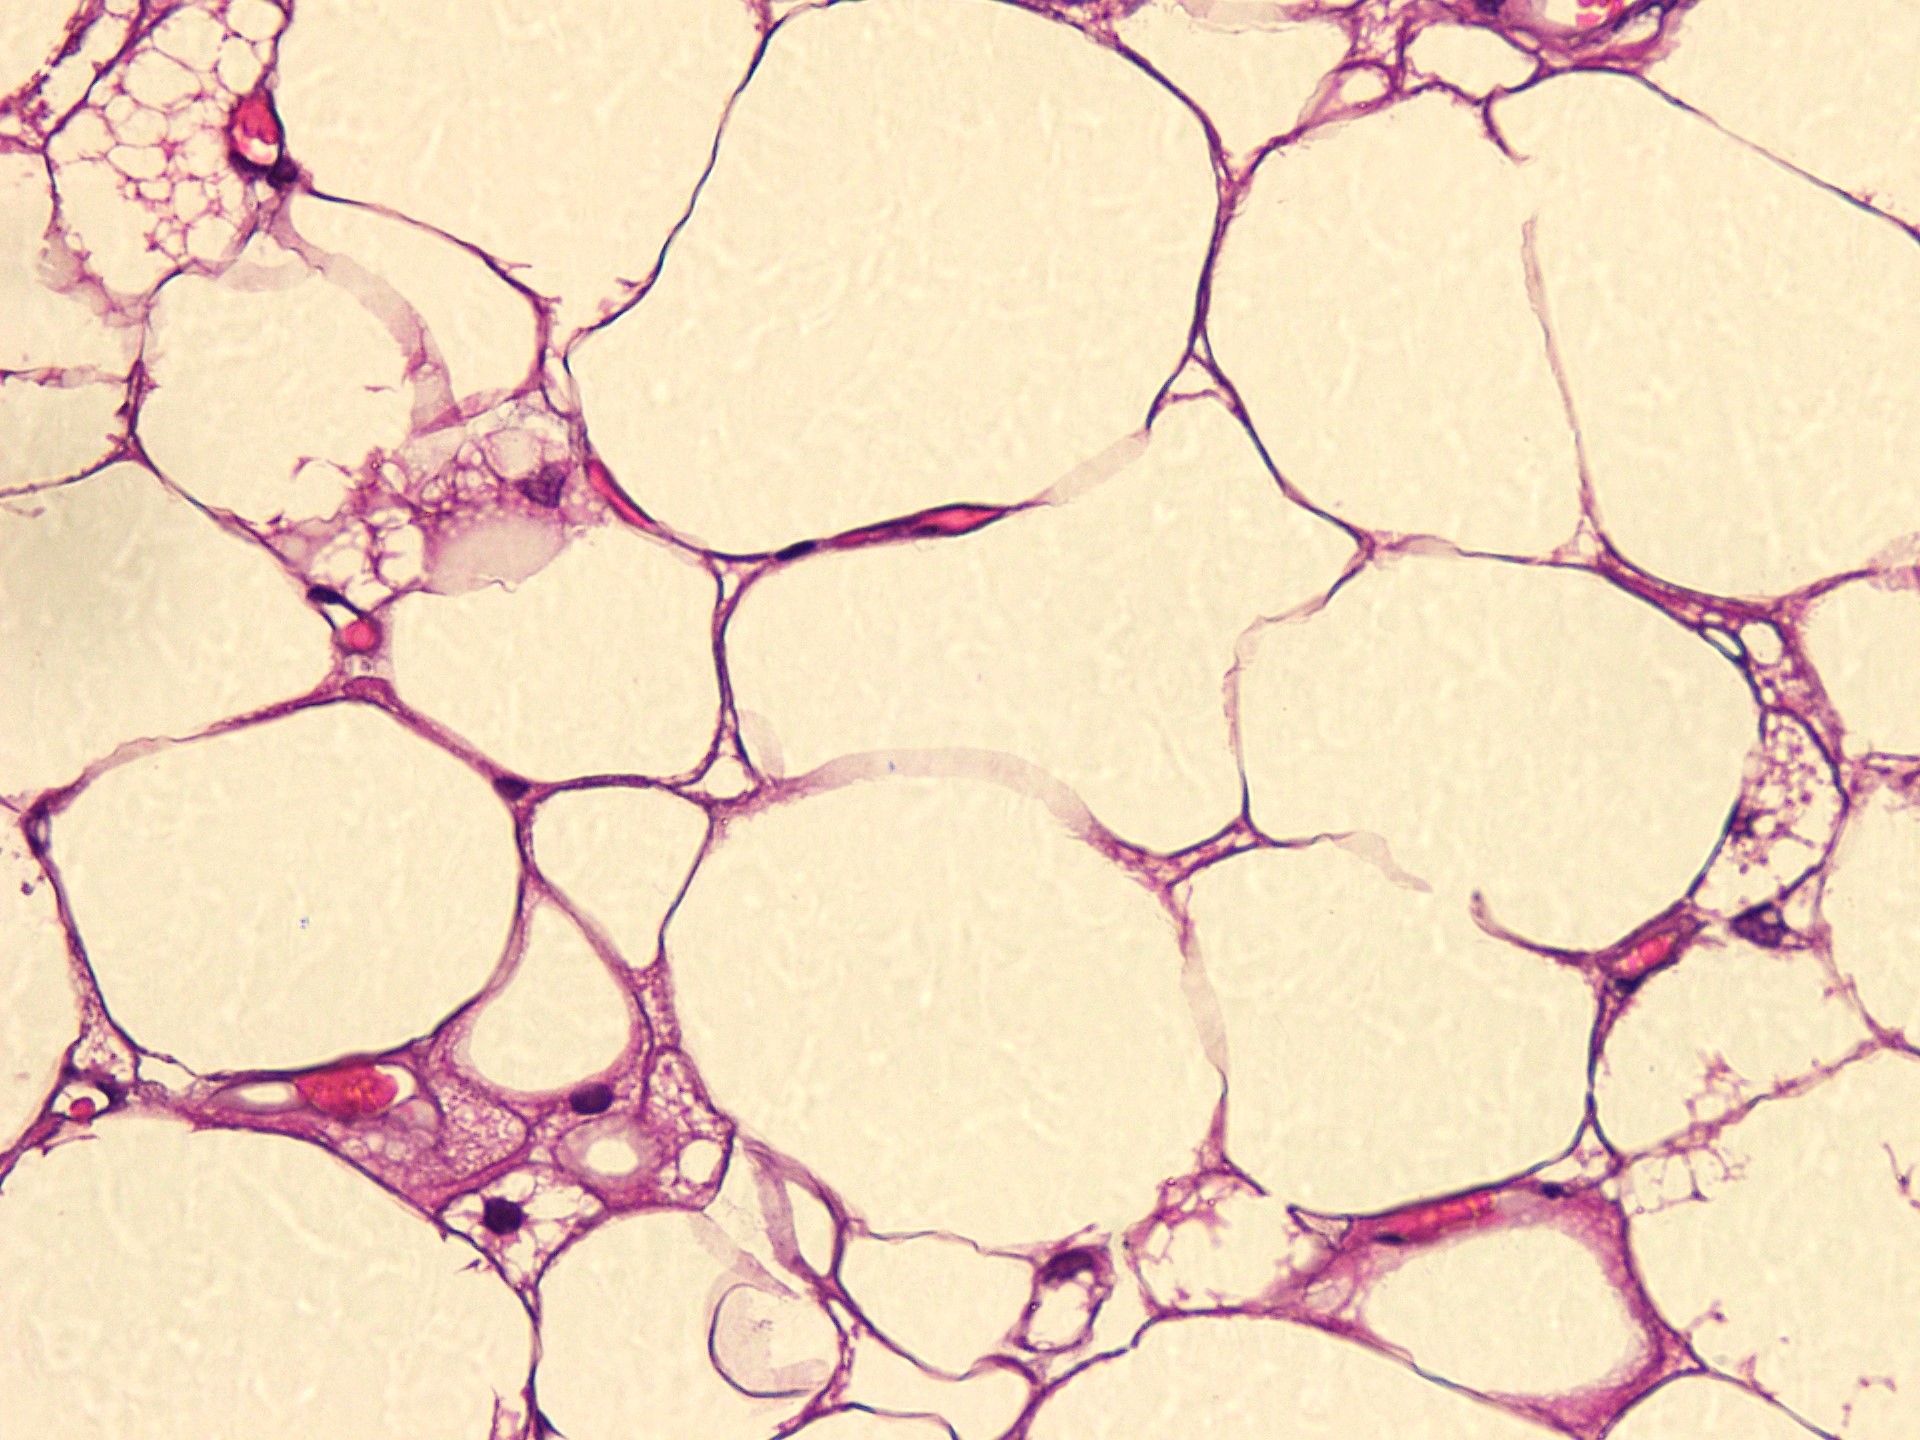

Microscopic (histologic) description

- Neoplastic lesion composed of polygonal brown fat cells with stromal cells in the background (Case Rep Oncol 2017;10:438)

- Large number of pale and eosinophilic brown fat cells with multivacuolated, eosinophilic granular cytoplasm and small central nucleus (about 70%) admixed with variable amount of univacuolated white cells (Case Rep Oncol 2017;10:438, Am J Case Rep 2020;21:e921447, J Comput Assist Tomogr 2019;43:793, J Pathol Transl Med 2017;51:499, Am J Surg Pathol 2018;42:951, Virchows Arch 2021;478:527)

- Multivacuolations resemble lipoblasts

- Morphological variations or subtypes: typical, myxoid (9%), lipoma-like (7%), spindle cell (2%), thick bundles of collagen fibers, presence of mast cells and exclusively containing brown fat cells (Case Rep Oncol 2017;10:438, Am J Case Rep 2020;21:e921447, Virchows Arch 2021;478:527)

- Cytological atypia, necrosis and mitosis is unusual (J Pathol Transl Med 2017;51:499, Am J Surg Pathol 2018;42:951, BMC Surg 2021;21:30)

Microscopic (histologic) images